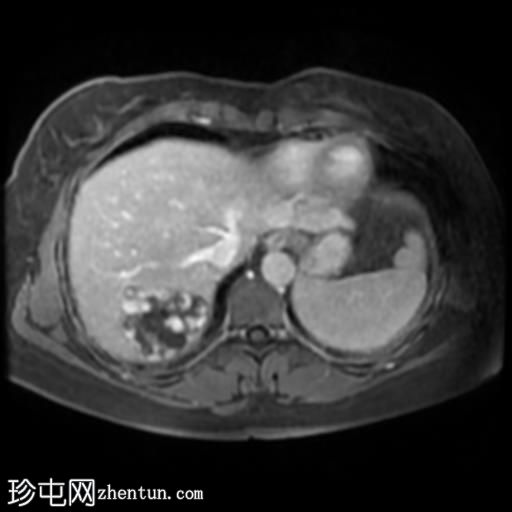

轴位T2加权像

脂肪抑制序列

肝脏第7段可见一边界清晰的分叶状肿块。T1加权像呈低信号,T2/T2脂肪抑制序列呈高信号,动脉期呈不连续结节状周边强化,门静脉期呈向心性强化,延迟期完全强化。DWI序列呈高信号,ADC值呈混合信号。